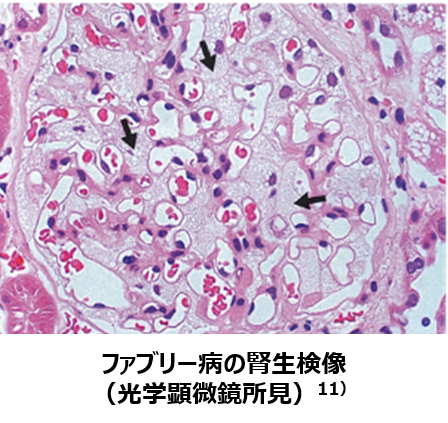

・光学顕微鏡所見では、糸球体たこ足細胞の腫大と胞体空胞化が特徴的であるが、空砲は他の細胞にも認められます9) 。

11)衞藤義勝 総監修 ファブリー病 基礎から臨床までの最近の知見⑦